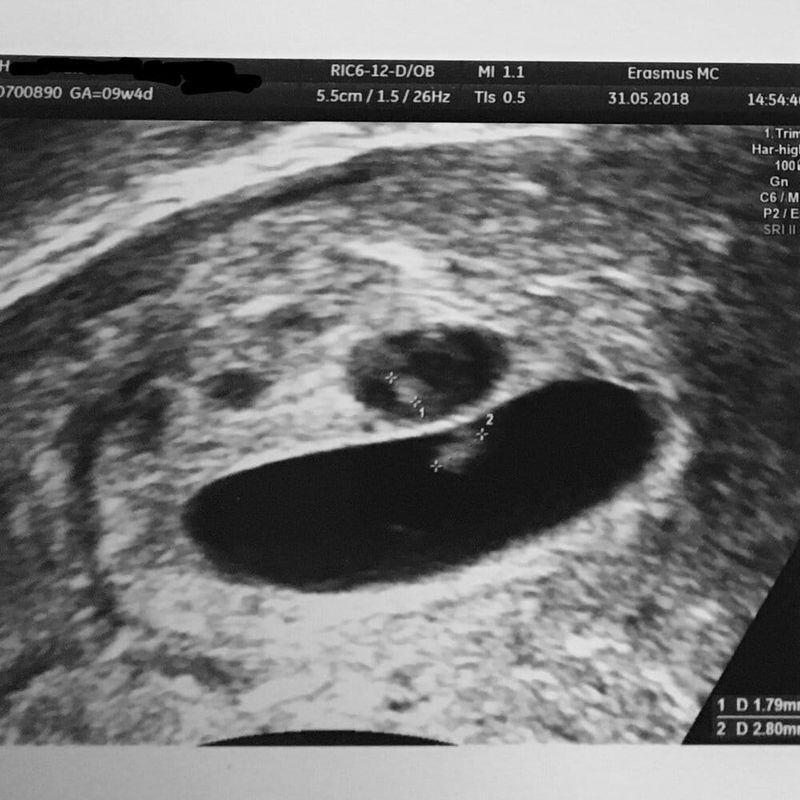

De artsen zeiden allemaal wat anders, waren er nou één, twee of toch drie vruchtzakjes?!

Ik was zenuwachtig. Het vruchtzakje zat er nog. Ze zei dat er hartactiviteit te zien was, maar het was te langzaam voor bijna één week verder. Dit kon twee dingen betekenen: het hartje was nog maar net gaan kloppen of deze zwangerschap was toch geen goede zwangerschap. Ook zag ze een tweede vruchtzakje en wees het aan op het scherm. Maar daar hoefde ik me geen zorgen over te maken. Dat zakje was leeg en het verschil in grootte was substantieel te groot om er iets van te maken. En ook wees ze nog een derde zakje aan, maar dat was echt heel klein. Verward zat ik in de auto. Toch wel zwanger, een vruchtzakje gezien met hartactiviteit maar het ging te langzaam. En hoe zat het dan met het tweede vruchtzakje? En het derde vruchtzakje? Ze had het wel gezien. Maar leeg. Ik hoefde me er geen zorgen over te maken zei ze. Zorgen? Ik had geen idee wat er allemaal door mijn hoofd ging. Ik weet wel dat mijn allerliefste vriendin ‘s avonds langs kwam met haar man om naar ons nieuw gekochte huis te kijken.

Het was alweer een tijd na de eerste ontdekking van mijn zwangerschap. In mijn hoofd dacht ik aan vruchtzakje twee dat leeg was en te klein en mogelijk een derde vruchtzakje. Het was bijna 15 uur toen ik aan de beurt was. Ook hier een inwendige echo voor beter beeld en wat zag ik op het scherm?! “Ik zie twee knipperlichtjes, klopt dat?”, riep ik. “Ik focus eerst even hierop”, zei ze, “maar wat jij zegt, heb ik ook gezien.” Ze ging kijken. Op het beeld klopten inderdaad twee hartjes. Twee knipperlichtjes. Ik begon te huilen. Ik had geen idee waarom ik huilde. Was ik bang? Was ik blij? Dacht ik toch ineens aan het derde vruchtzakje? Dat nu ook misschien toch ging ontwikkelen? Ik dacht aan gisteren. Dat ze zei dat het tweede vruchtzakje substantieel te klein was ten opzichte van het andere vruchtzakje en nu dan dus tóch een tweeling? Ik weet dat de verloskundige tegen me zei dat meer moeders soms wel schrokken in het begin. Maar het was niet echt de schrik waarom ik toen huilde. Dat weet ik nog zo goed. Misschien voelde ik aan wat er allemaal zou gaan gebeuren….